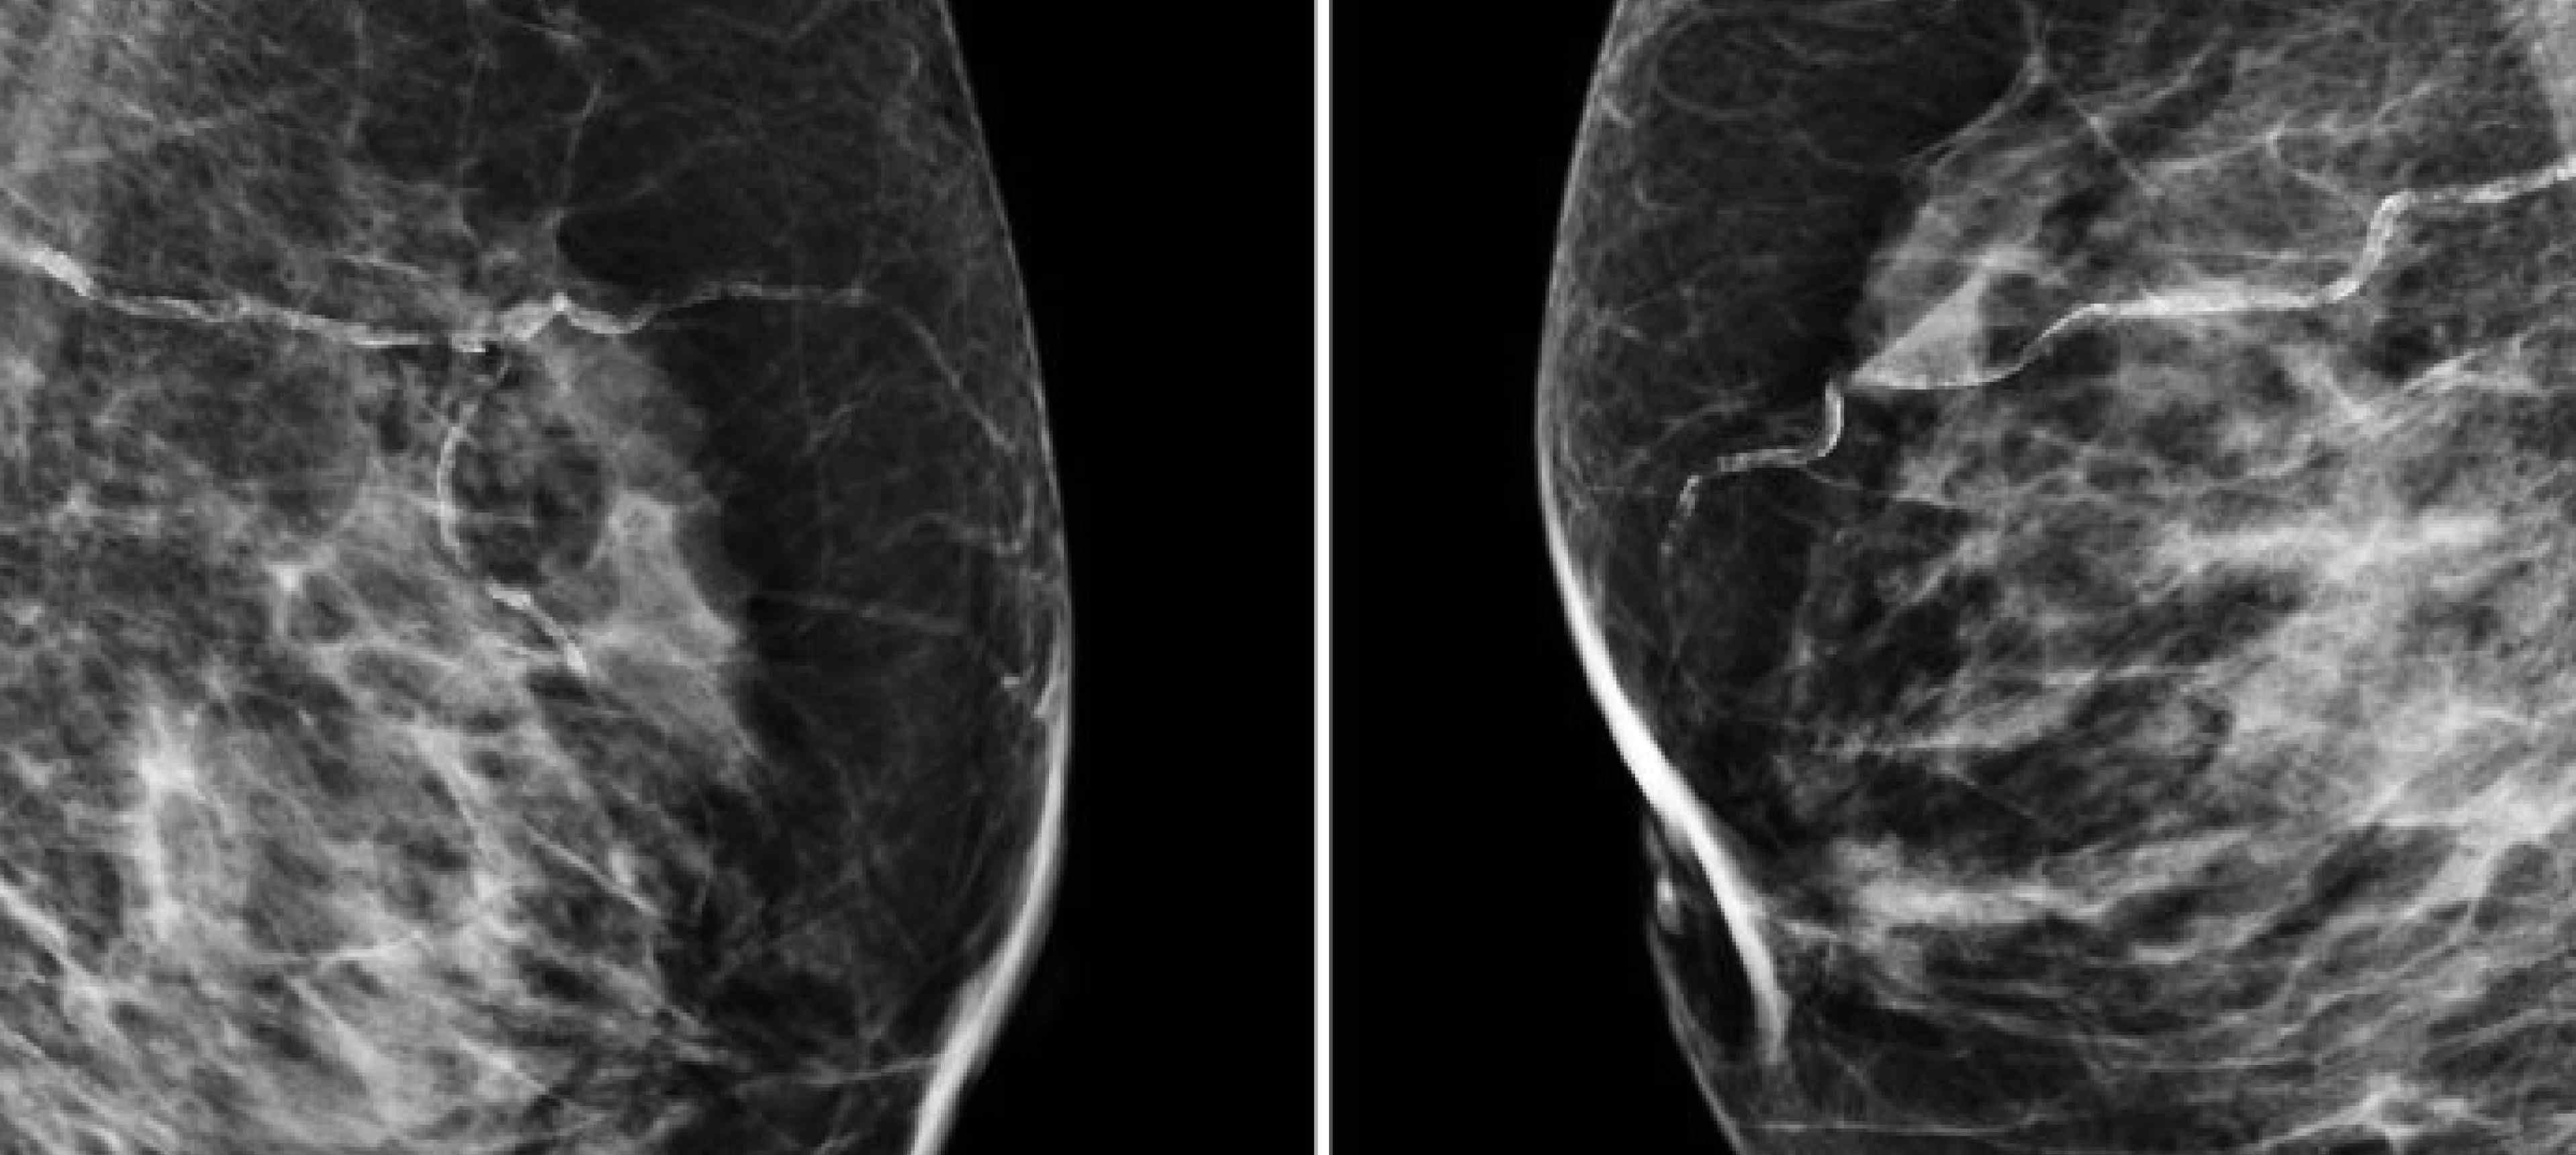

AI and Breast Cancer

Researchers from Imperial, Google Health, DeepMind, the NHS and Northwestern University have shown that a computer algorithm is as effective as human radiologists in spotting breast cancer from x-ray images. Image Credit: The CRUK-funded OPTIMAM database.